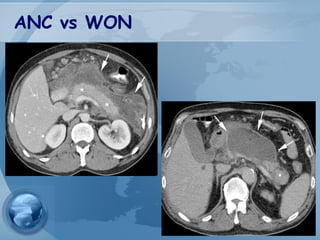

Acute Necrotic Collection(ANC)

• A collection of both fluid and solid

components (necrosis) occurring during

necrotizing pancreatitis.

• This collection can involve the pancreatic

and/or the peripancreatic tissues

• CECT Criteria

– Heterogeneous

– No encapsulating wall

Walled-Off Necrosis(WON)

• A mature, encapsulated ANC with a well-

defined inflammatory wall

• these tend to mature >4 weeks after onset of

– Heterogenous

– Well-defined wall

– Intrapancreatic and/or extrapancreatic

ANC vs WON